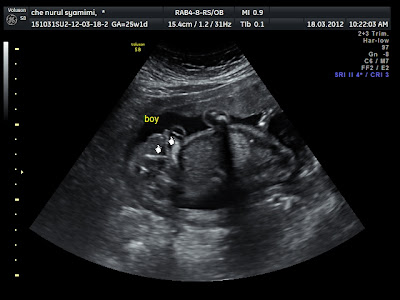

ktorang dah booking nk scan 3d dengan miss jeezlyn. saya google2 je. pastu ramai cakap best. murah. berbaloi2. saya ni kan tukang google pastu tukang report pape kt husband. husband tukang bayo je. ehehe. saya booking kt Facebook 3D 4D Scan Malaysia. ahad miss jeezlyn ada kt Hospital UMRA Seksyen 13, Shah Alam. slot saya pukul 10am. smp je diorang buat macam checkup plak. siap timbang, amek urine test. tunggu kejap. masuk la dalam bilik nk scan. cantik woo. spital dia. Miss Jeezlyn ni baik sangat. mmg best! scan je dia terus cakap. "oo. ini sula nampak dia punya jantina ni" *baca dengan nada slang cina. hehe. eh main2 plak. dan betul la kot........

boboiboy!

pastu scan 3D baby tak mo tunjuk mukaaaa!! baby pemalu orangnye. baby macam ayah kot. tak suke orang amek gambo. klau baby macam ibu. sah2 baby sengih je tengok camera. kuang3. Miss Jeezlyn lama kot pujuk die suh tunjuk muka. dia tutup da. dua-dua tangan dok kat kepala. mesti bby cakap. takmo takmo! *ok. ibu over* haha,.

Lepas pusing2 scan nk tengok dia. die still dok pusing kedalam. taknak tunjuk muka. time tu dah lebih 20 minit. dah nk dekat sejam. Miss Jeez suruh pegi keluar makan something and jalan2 dulu. Mak buyong gagahkan diri jugak la. makan roti minum air sikit. pastu dalam 15 minit camtu. die call balik. masuk scan lagi. ok la sikit. baby at least tunjuk la sipi2 muka tembam die. hehehe. tembamm pipi nyee~

tadaaa! saya tengah hisap jari la ibu. lapar ye anak ibu. cian

lepas scan 3d. saya continue scan detail which is Miss Jeez buat dalam 2d. detail scan ni die check anggota badan. kira jari kaki cukup tak 10. kira jari tangan pulak. check semua2 la. otak. organ2 dalam. nk cakap lebih pon tak reti term2 doctor ni kan. hehehe.

jantung. penting utk tahu ada penyakit jantung berlubang ke tak.

Miss Jeez cakap baby kecik sikit dari scale normal. tapi masih tak lari sangat. die kecik about 100g je. dalam graft pon nampak die ke bawah sikit. so far, kepala baby dah kt bhgian bawah. mintak2 jgn pusing ke atas ye baby. Miss Jeez tetap cakap, chances untuk baby tukar position still ada. tp kurang. Ya Allah, kau permudahkanlah semua.